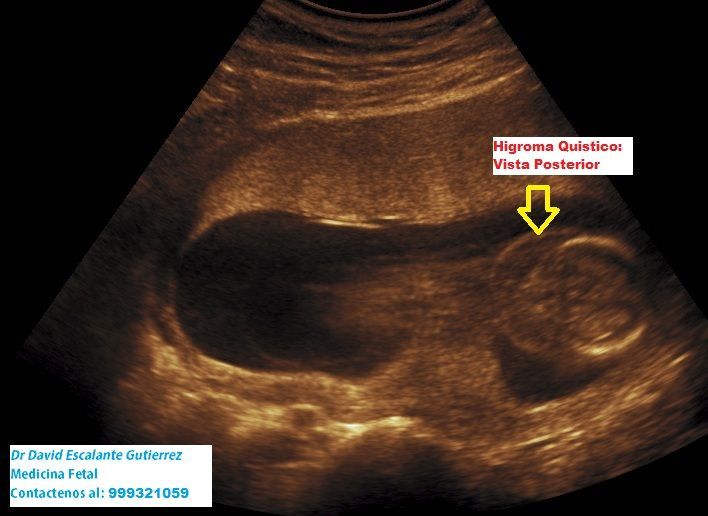

Realizamos las ecografías de viabilidad del embarazo, genética, morfológica, de bienestar fetal, ecocardiografías fetales, así como procedimientos invasivos como biopsia de vellosidades coriales y amniocentesis.